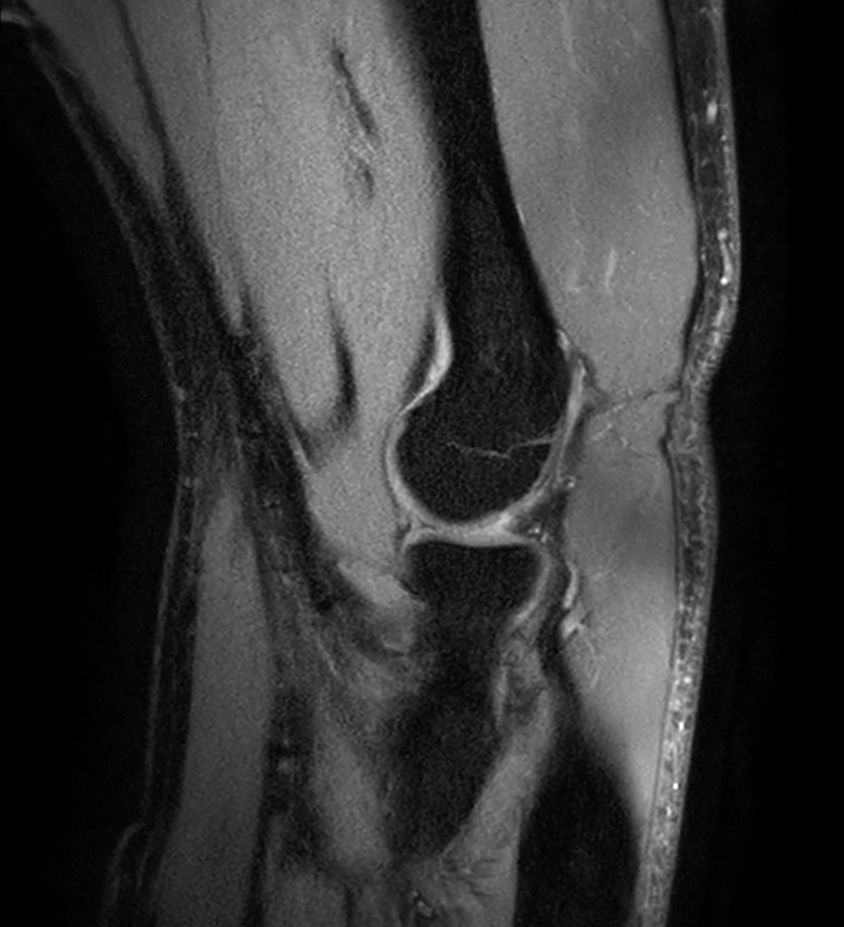

Coronal T1w mDIXON XD TSE (Water only)